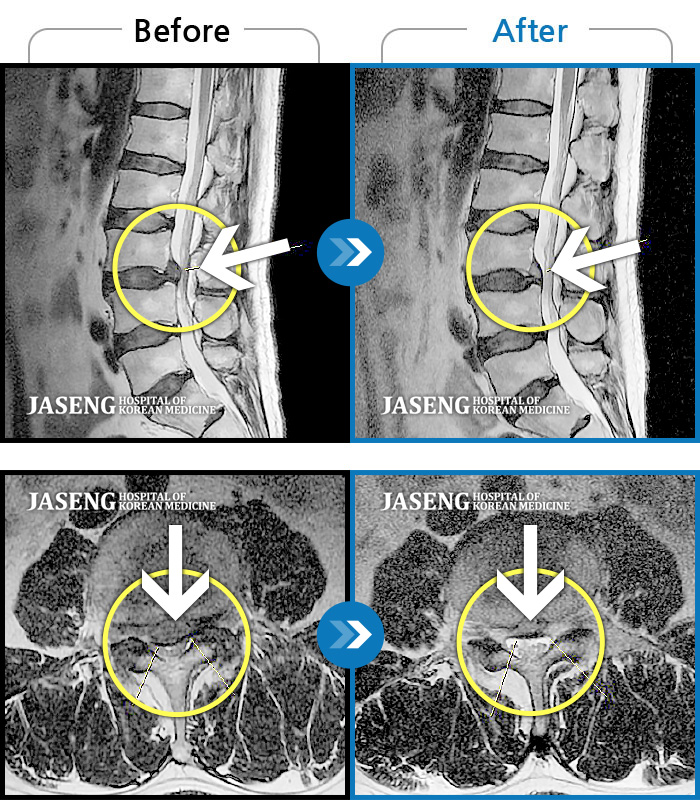

MRI 치료사례

양 허리와 다리가 아프고 걸을때 다리 통증으로 걷기 어려웠다